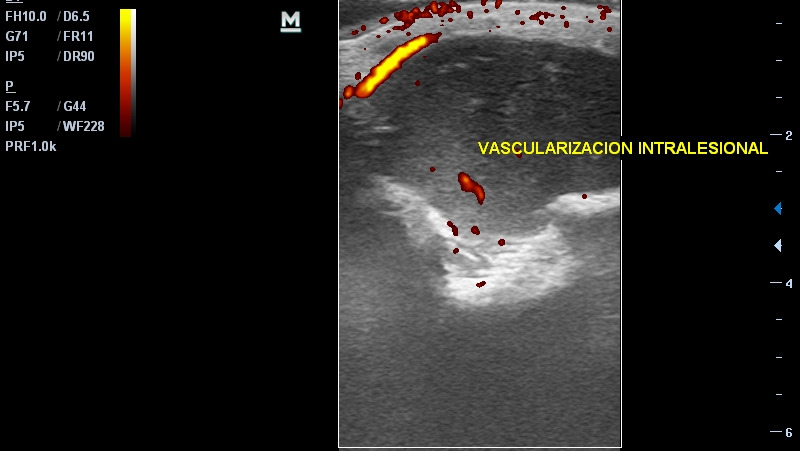

Hola, me llamo Gael. Estoy recaudando fondos y requiero de tu ayuda porque necesito operarme nuevamente del brazo. Ya fui sometido a una intervención quirúrgica en la que se removió una lesión tumoral que me salió en la muñeca derecha. Gracias a una biopsia que requirió una intervención quirúrgica ambulatoria, descubrimos que se trataba de un tumor de CÉLULAS GIGANTES. Aunque se supone que tiene carácter benigno, fue muy agresivo: empeoró muy rápidamente después de la primera biopsia (me hicieron una segunda en Caracas para confirmar), provocó gran pérdida ósea y tenía potencial de malignidad si no se atacaba inmediatamente. El tumor que se removió pesó aproximadamente 2 kilos. Gracias a Dios, la tercera biopsia de la pieza confirmó nuevamente el diagnóstico, lo que permite que me hagan cirugía reconstructiva y no una amputación, que estuvo entre las opciones médicas propuestas. Sabemos desde ya que perderé la movilidad de la muñeca. Los doctores aún están decidiendo el plan quirúrgico: están entre hacerme un raspado óseo del peroné para insertarlo en el radio (hueso del brazo que se vio afectado) para que se solidifique, o colocarme el cúbito de manera central, para que sea el único hueso de mi antebrazo. Parece que tienden hacia la segunda opción, dado que la pérdida ósea es de al menos 10 centímetros. La primera se trató de una operación de gran envergadura, que duró más de ocho horas y requirió de un gran equipo especializado: cirujano, especialista en cirugía de mano y especialista en tumores óseos, además de varios doctores asistentes. Logramos manejarlo a través de la salud pública, en el Hospital Pérez Carreño, en Caracas. La salud en mi país, Venezuela, lamentablemente está en situación de crisis y a pesar de contar con profesionales de gran talla, todos los insumos quirúrgicos y medicamentos deben ser cubiertos por mi familia. Eso sin contar el hecho de que hemos tenido que permanecer más de un mes fuera de nuestro hogar en una ciudad ajena y haciendo diligencias que requieren muchos gastos de movilización. He contado hasta ahora con mucha solidaridad de amigos, vecinos, familiares e instituciones, pero aún necesito un poco más de apoyo para concluir esta etapa amarga de mi vida y recobrar mi salud, dentro de las posibilidades. Soy diestro, así que esta lesión ha complicado mi calidad de vida y mis posibilidades de movilidad, al igual que mis actividades como atleta. Sin embargo, estamos esperanzados porque al menos no se trató de un carcinoma (lo que se temió antes de las biopsias) y no necesitaré tratamientos químicos, tan solo otra intervención quirúrgica, que si bien es de gran envergadura, será realizada por un excelente equipo médico en el que confío plenamente para ayudarme a recuperar mi salud. Si está dentro de tus posibilidades ayudarme con una donación, te estaré agradecido eternamente; cualquier cifra es bienvenida por pequeña que sea: todo suma. También te agradezco la difusión de esta información por todas las plataformas que te sean disponibles, así como los posibles contactos con instituciones gubernamentales o benéficas que puedan ayudar. Todos los aportes serán eternamente agradecidos. De igual manera, si estás en situación de DONAR SANGRE en la ciudad de Caracas, ese aporte también será bienvenido. Dios te bendiga y reponga tu ayuda en salud y bienestar. Si quieres donar en *bolívares*, puedes hacerlo a la cuenta de mi mamá: Alejandra González Poleo Provincial Corriente 0108 0977 1701 0020 5079 Para pago móvil: Ci 14491428 Telf 04125384544 Si quieres donar en *Euros* puedes hacerlo a la cuenta de mi papá: Fernando Enrique López González: ES7820800144853000032790 (Abanca) Si quieres donar en *Zelle* o donar *sangre* comunícate con mi mamá al +584125384544 y ella coordinará para hacer efectivo tu aporte. También puedes donar en el sitio GoFundMe. Mil gracias!!! https://gofund.me/3bf10d25